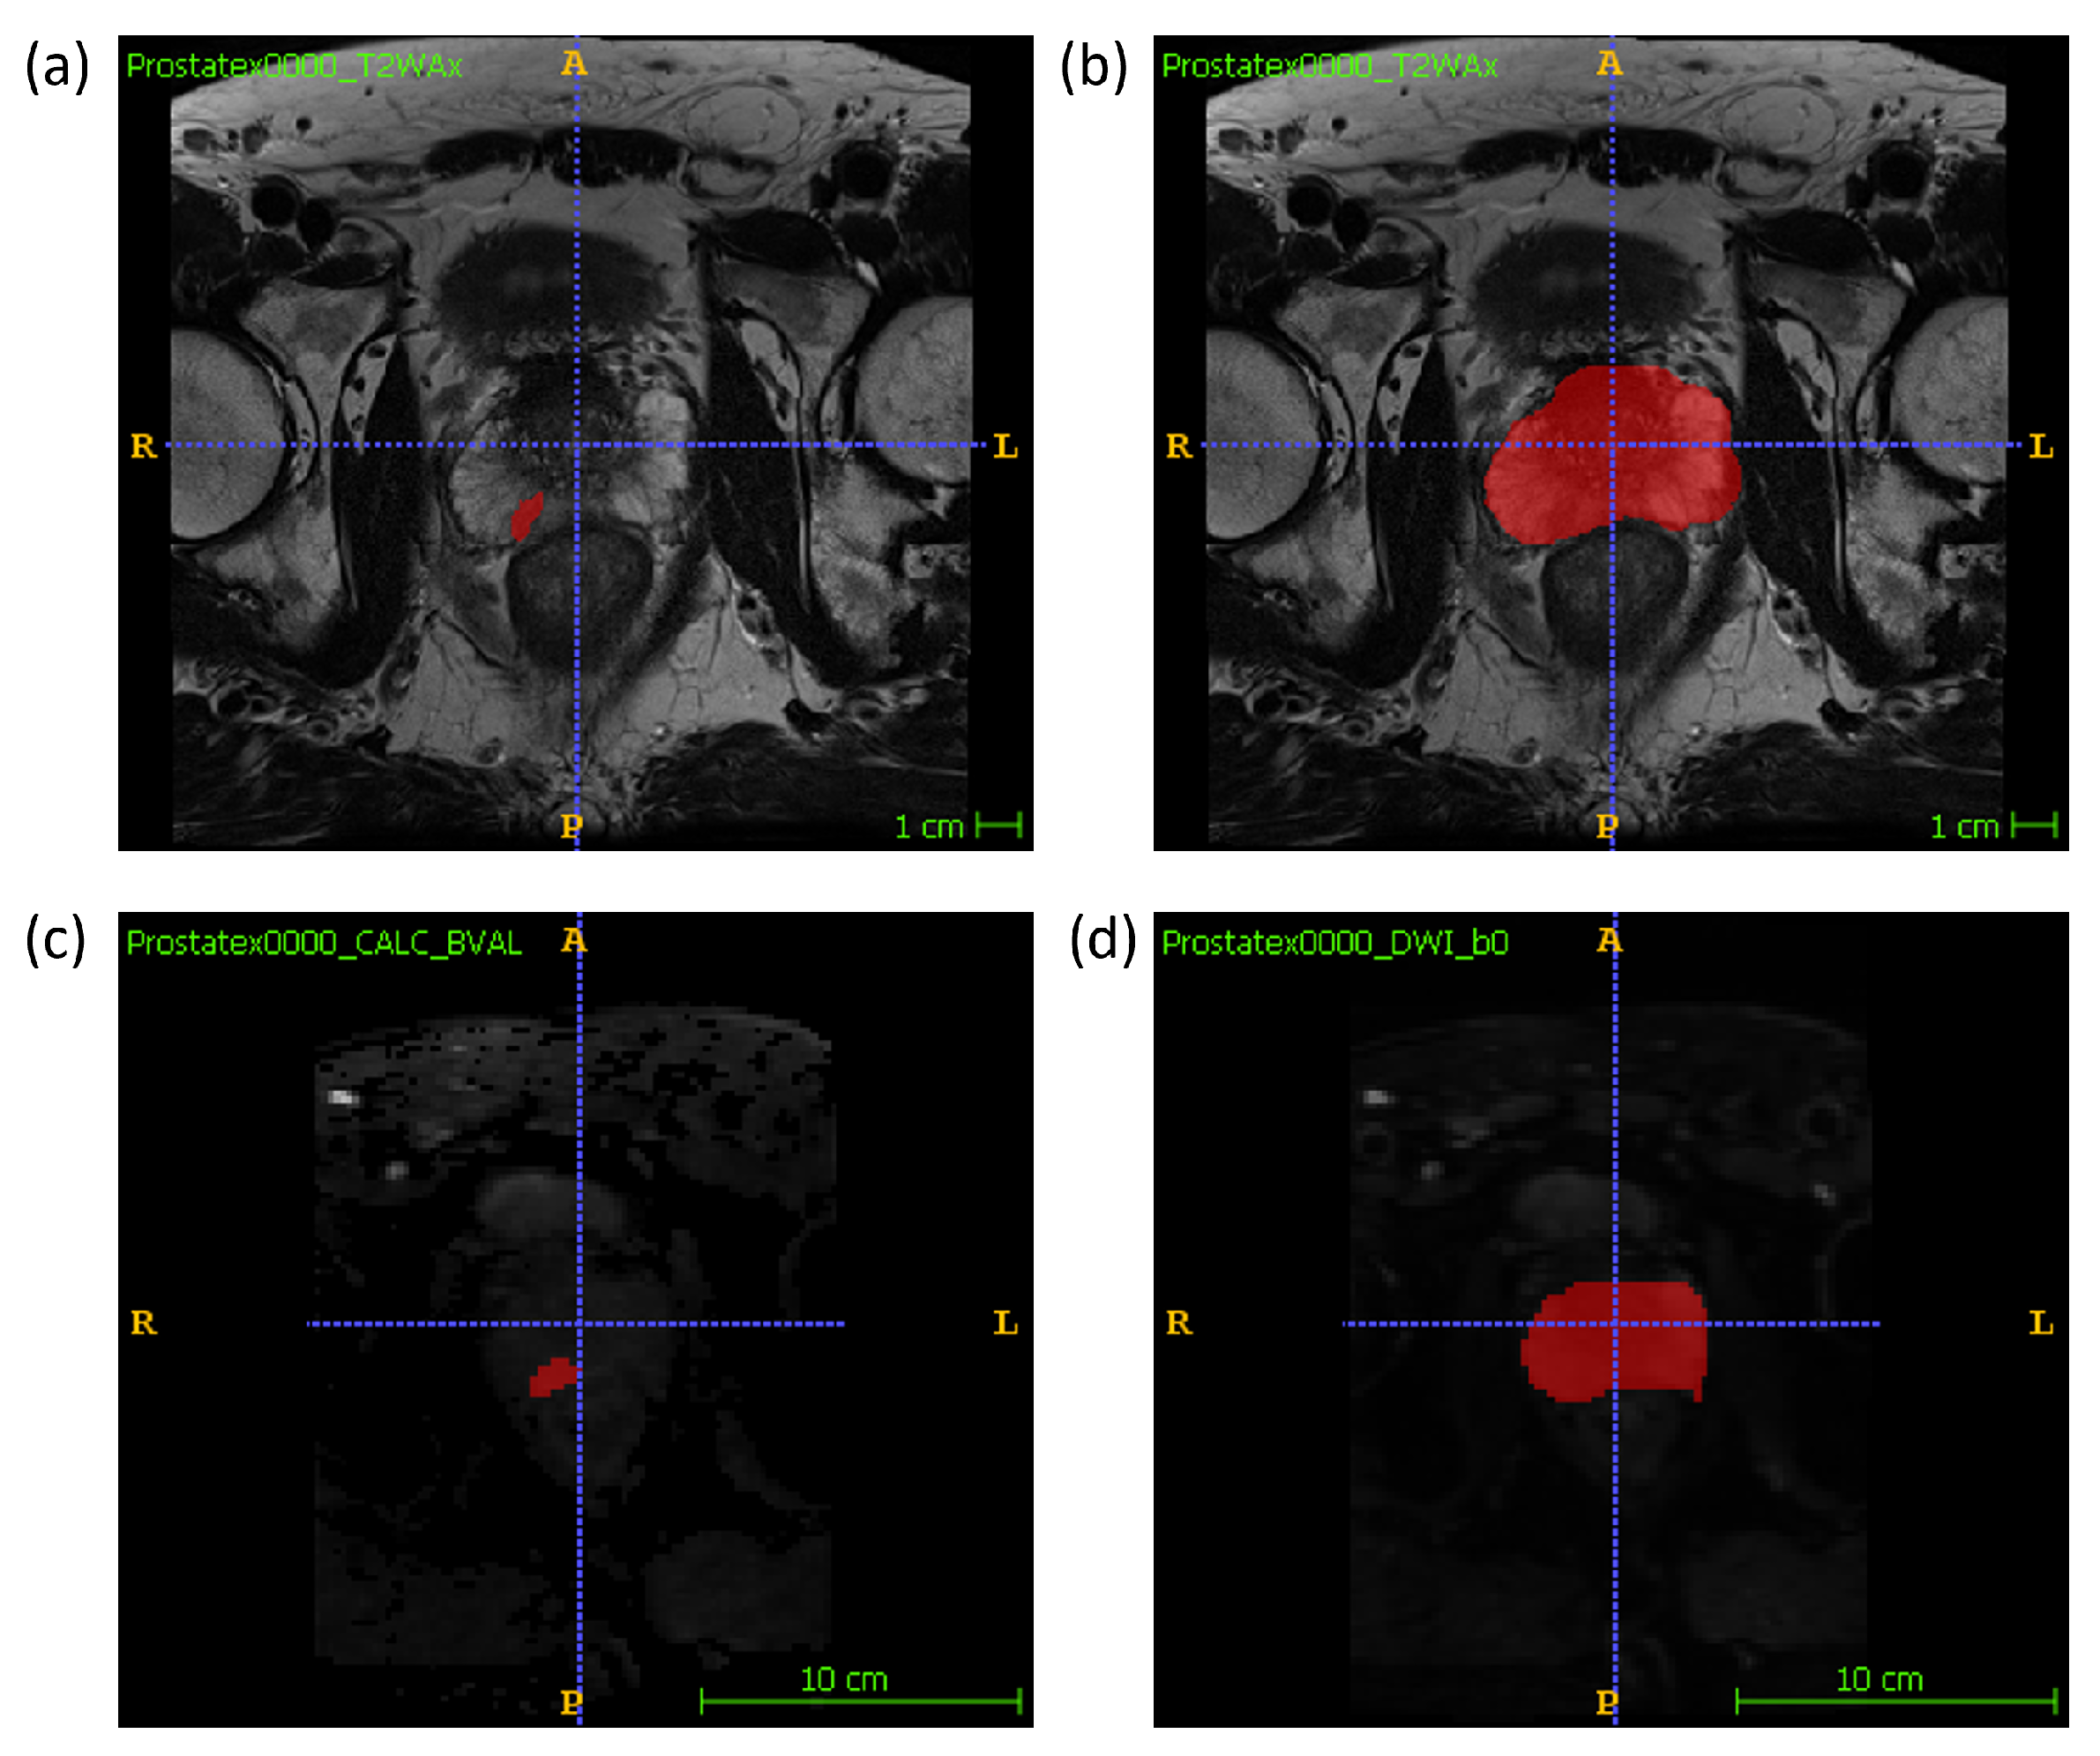

2.1. Data Description

2.2. Feature Extraction